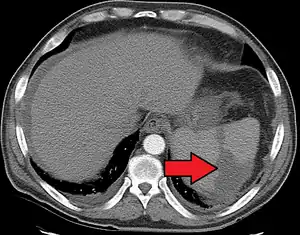

| Splenic infarct seen on CT | |

An abdominal CT scan is the most commonly used modality to confirm the diagnosis,[3] although abdominal ultrasound can also contribute.[4][5][6]